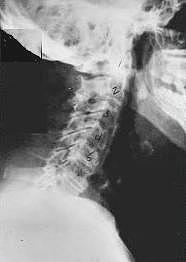

Phase Three - Subluxation Degeneration

Subluxation Degeneration - Phase Three Phase Three Subluxation Degeneration is caused by subluxations that have been continuing on for between 40 and 65 years. This phase has all of the attributes of the previous phases, only worse. The curvatures are abnormal, the disc spaces are vastly decreased and changed. Calcium changes on the spine are abundant in this phase. Normally, people in phase three have a restricted range of motion and probably exhibit symptoms of some kind. In phase three the vertebrae show obvious changes and mutations in shape. Projections made of calcium, sometimes referred to as "spurs or lipping", can be readily seen on x-ray. Chiropractic reconstructive care for patients in phase three ranges from 2.5 years to 3.5 years. This does not mean that at the end of this time that any or all of the calcium changes will be gone. In many instances the body adapts to the presence of the calcium and positive changes can only be measured from a functional standpoint. As before, if Phase Three Subluxation Degeneration is left unchecked it slowly advances onward into the next phase.